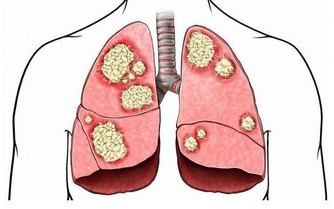

1、 出伏養肺潤一點出伏過後雖然中午依舊熱,但是早晚氣溫慢慢要降下來了,晝夜溫差逐漸增大,開始走向秋季的過度期,氣候逐漸變得乾燥,人體的肺氣相對開始變得旺盛,而中醫認為“肺氣太盛可克肝木,故多酸以強肝木”。因此要多吃些滋陰潤燥的食物,避免燥邪傷害,這個時候飲食上要潤一點。

這時候飲食裡要加潤燥食物,例如白蘿蔔。中醫理論認為白蘿蔔性屬涼,入肺胃經。白蘿蔔富含葡萄糖、蔗糖、果糖、維生素C、萊菔甙等,其中的芥子油、澱粉酶和粗纖維,具有促進消化,增強食慾和止咳化痰的作用。